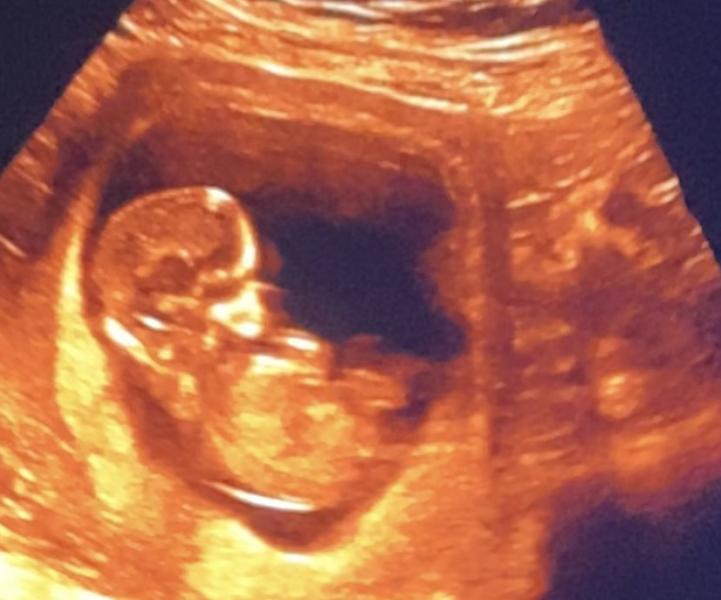

Сегодня сделали первый скрининг

12,3 пдр на 20.06.25.

По плоду все отлично, показатели все в норме.

Чсс 154 ктр 59